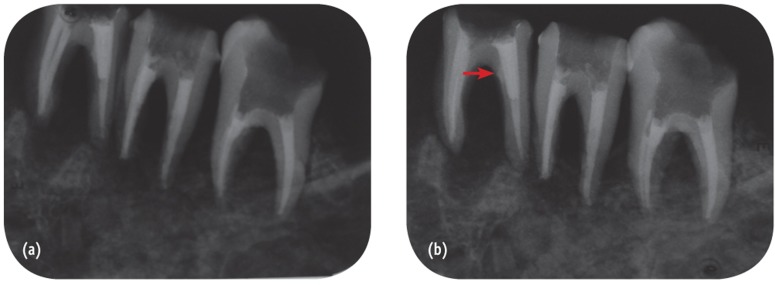

Intraoral conventional and digital radiography were done using E Speed dental films (Kodak, Rochester, NY, USA) and Digora Optime (Soredex, Tuusula, Finland) size 2 PSP receptor (85 - 167 microns pixel size and 6 - 8 LP/mm resolution) with Minray intraoral x-ray unit (Soredex). To hold the image receptors in a fixed and repeatable position, a film holder was made with putty paste (Asia Chemi Teb Mfg Co., Tehran, Iran). The mandible was placed on a table and mounted on a wooden block to facilitate the movement of the x-ray tube. Two images were taken from each tooth in two different directions including perpendicularly and 10° distal tube shift relative to the long axis of the teeth. Exposure times were 0.2 and 0.12 seconds for conventional and PSP radiography, respectively, with the exposure settings of 7 mA and 60 kVp. Conventional radiographs were processed in an automatic processor (Hope DentalMax X-ray processor, ClassicXray. com, Rolla, MO, USA) and then mounted (Figure 2). Digital receptors were kept inside a black plastic bag to minimize the effect of environmental light and were then scanned using a Digora scanner (Soredex). The images were stored in JPEG format (Figure 3).

In our study, the diagnostic value of periapical radiographs in diagnosing strip and root perforations was high mainly because these perforations were made on mesial or distal sides of the roots and radiopaque materials were placed in canals. Although the diameter of perforations were small and similar to the diameter of endodontic instruments, the results obtained in the current study showed that the diameter of perforation did not influence the accuracy of periapical radiographs which is similar to a previous study.7 Changing the horizontal angulation of the radiation source increases the diagnostic ability of PRs especially for diagnosis of strip perforations where the location of perforation could be masked by the concavity of the root (Figures 2 and 3).7,34 Consequently, it was possible to highly diagnose strip and root perforations.